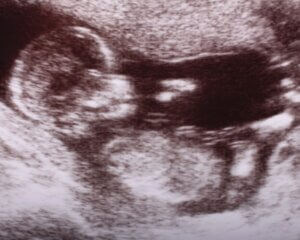

Ultrasounds are incredibly safe for staying informed about your baby’s health and growth.

Pregnancy ultrasounds are safe and painless tests that use sound waves to make images that show the baby’s shape and position.

Ultrasounds can be done safely throughout your pregnancy for an early pregnancy assessment or growth scans later, even if you’d just like to see your little one once more.